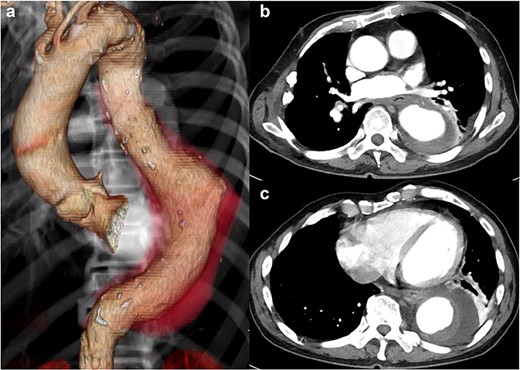

The patient had no back pain when he came to our hospital. His laboratory data on admission indicated severe infection, i.e. a white blood cell count of 15 080 cells/μL and C-reactive protein of 24.9 mg/dL. CT angiography showed an aneurysm, measuring 50 × 57 mm, with an effusion around it (Fig. 1). Because a mycotic aortic aneurysm was strongly suspected, intravenous antibiotic therapy was started with tazobactam/piperacillin hydrate, despite negative blood cultures.

CT shows a descending aortic aneurysm (a), 50 mm in diameter (b), surrounded by an effusion (c).